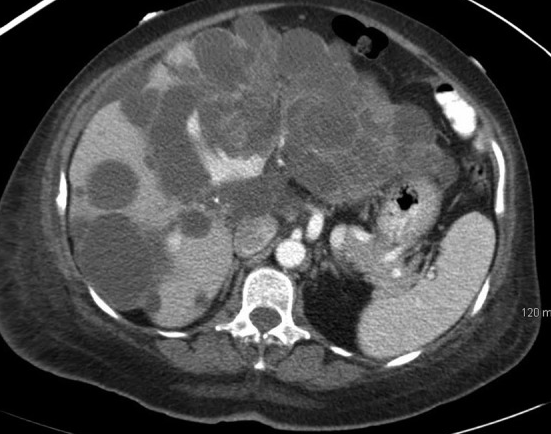

Polycystic liver disease. Red arrow. Infected hepatic cyst (Courtesy Dr. V. Penopoulos)